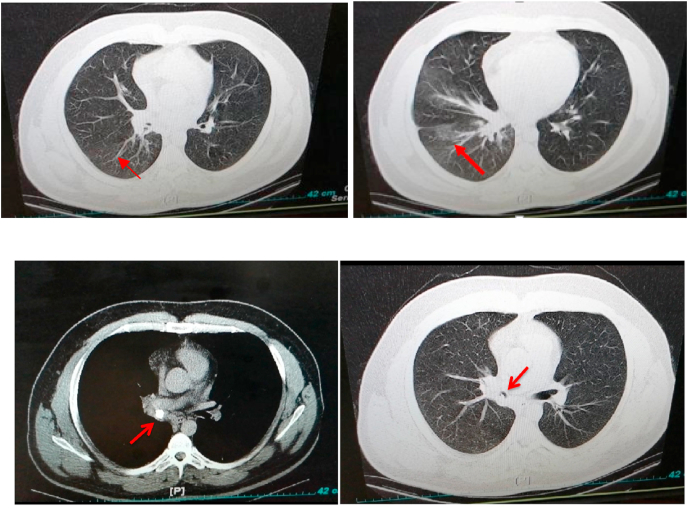

After 5 days, the patient's general condition improved and he was discharged to his own personal satisfaction. However, he was referred to our hospital 24 hours later due to the persistence of his cough and SOB. He was admitted under the supervision of a pulmonologist, and HRCT and RT-PCR were ordered. The result of the lung HRCT showed mosaic attenuation in the right middle and lower lobes due to air trapping (Fig. 1). In addition, the RT-PCR for COVID-19 was negative. Moreover, the results of the chest X-ray (CXR) revealed a round opacity in the right main bronchus (Fig. 2). Clinical suspicion was placed on the FBA based on the radiologist's comment (Fig. 1, Fig. 2). Rigid bronchoscopy was performed to further investigate and diagnose the patient, and an olive kernel was discovered in the right main bronchus (Fig. 3 A, B).

Fig. 1.

The result of lung HRCT showing mosaic attenuation in the right middle and lower lobes (arrow head) due to air trapping.